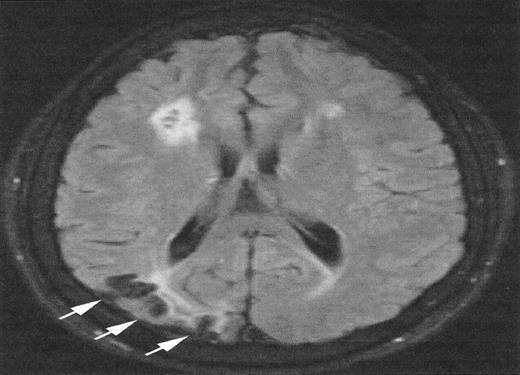

Other MRI observations in sickle cell disease

The relationship between SCI and other patterns of brain injury that can be seen in children with SCA is not well defined. In part, this is because SCI can only be identified with surveillance MRI evaluations, which have only recently become routine in some clinical centers. A common finding is cerebral atrophy. This is a non-specific finding that serves as a marker for disease severity in the brain. Another common finding is Moya-Moya, a description that comes from the Japanese for “puff of smoke” because of the angiographic appearance of secondary extensive collateral formation. Figure 2 is a time-of-flight MRI angiogram in a child with SCA and Moya-Moya. The arrows indicate the stenosis/occlusion of the distal internal carotid arteries. The child with SCA and Moya-Moya shown in Figure 3 has an extensive area of cortical infarction corresponding to the distribution of the posterior cerebral artery (arrows) and silent cerebral infarct in the frontal regions.

Magnetic resonance imaging (MRI) from a child with sickle cell anemia (SCA) and Moya-Moya.

The severe hemodynamic compromise associated with the Moya-Moya vasculopathy is associated with overt stroke secondary to a right parietal cortical infarction (white arrows). The signal hyperintensities in the frontal regions correspond to silent cerebral infarctions.